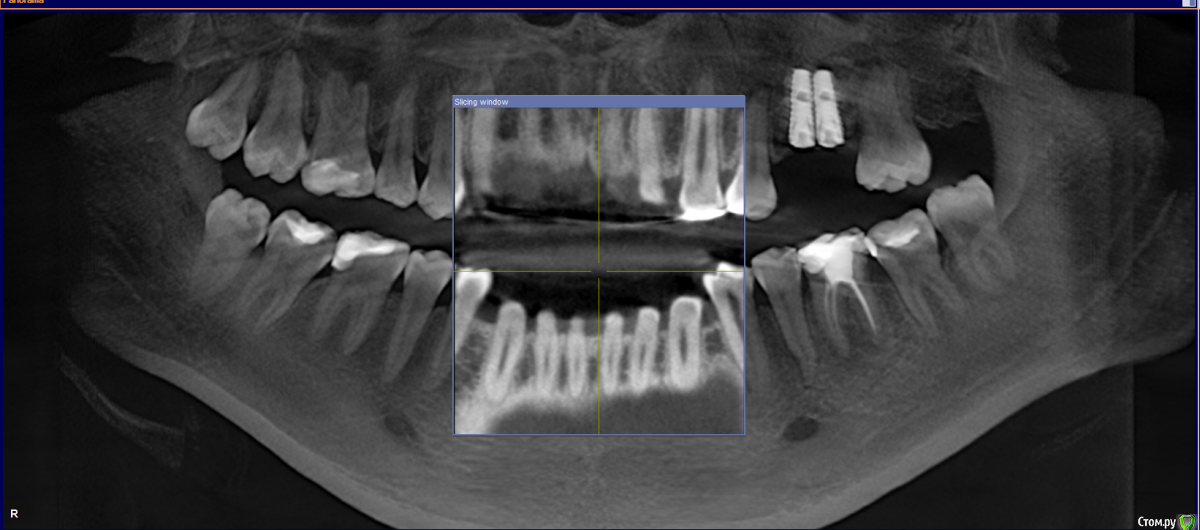

layraldo Опубликовано 4 декабря, 2019 Поделиться Опубликовано 4 декабря, 2019 Здравствуйте! Подскажите, пожалуйста, насчет ситуации. Весной этого года были установлены два импланта (вроде Nobel Biocare), перед этим был сделан синуслифтинг. Недавно пошла удалять зуб и там хирург, посмотрев на снимок челюсти, сказала, что импланты установлены неверно, очень близко друг к другу, и что они выпадут в течение года. Есть ли шанс, что они прослужат дольше и если прогноз неблагоприятный, то что делать? Врач-ортопед из клиники, где были установлены импланты ничего по поводу снимка не сказал. Ссылка на комментарий

dok1 Опубликовано 5 декабря, 2019 Поделиться Опубликовано 5 декабря, 2019 Если реалии соответствуют снимку, то близко Ссылка на комментарий

dok1 Опубликовано 7 декабря, 2019 Поделиться Опубликовано 7 декабря, 2019 Между имплантами нет полноценных кровеносных сосудов, соответственно нет питания и полноценной кости. Ссылка на комментарий